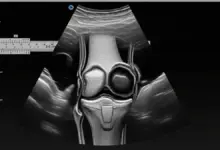

Quando ocorre perto do joelho, costuma acometer o planalto tibial (a “superfície” da tíbia que participa da articulação).

- Radiografias com carga (em pé): podem estar normais no começo, mas ajudam a ver alinhamento, artrose e sinais de colapso ósseo em fases mais avançadas.

- Ressonância magnética: é o exame que mais ajuda no início, pois mostra edema ósseo, alterações subcondrais, extensão da lesão e sinais de risco de colapso.